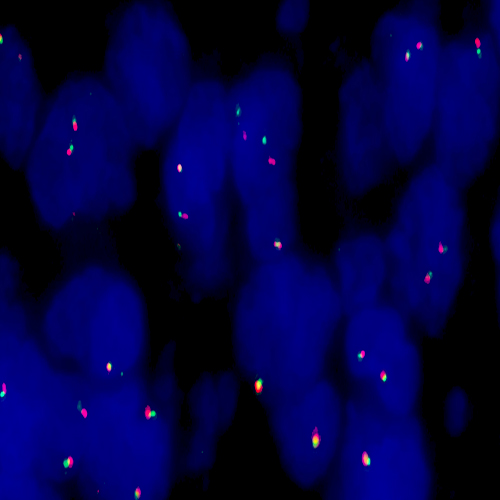

Diffuse Large B-Cell Lymphoma stained using Kreatech BCL2 (18q21) Break

XL probe for BOND (KBI-XL008).

BCL2 (18q21) Break - XL for BOND FISH probe detects genomic translocations involving the BCL2 gene. BCL2 (18q21) Proximal - XL and BCL2 (18q21) Distal - XL probes are optimized to detect the genomic regions proximal and distal to break points in the BCL2 gene region.

When combined, both probes are used to detect translocations involving the BCL2 gene at 18q21.